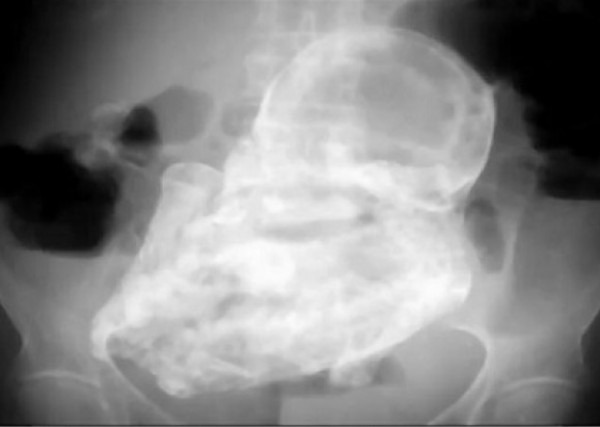

أخرج طبيب عراقي في مدينة كربلاء في العراق من بطن امرأة عجوز طفلة متحجرة منذ 40 عاماً بعد تقطيعها بواسطة منشار طبي في عملية تعد الأغرب من نوعها.

وصرح الطبيب الجراح صباح حسين الذي يعمل في المستشفي العام في كربلاء أنه أجرى عملية لإخراج الكيس من بطن امرأة عجوز تبلغ من العمر 70 عاماً وقد وجده متحجراً.

ولم يستطع الطبيب فتح الكيس إلا بواسطة منشار طبي حيث وجد بداخله طفلة متكاملة متحجرة.

وقالت العجوز أنها قبل 40 عاماً نُصحت من قبل الأطباء بإجراء عملية لأستخراج جنينها لأنه خارج الرحم لكنها لم تعمل العملية، مضيفة أنها من عائلة محافظة جداً وقد تزوجت العجوز وهي شابة فحملت وانجبت لمرتين بصورة طبيعية وفي الحمل الثالث كان عمرها 30 عاماً، مشيرة إلى أن هذا الحمل قد رافقه الكثير من الأوجاع والألآم عكس الحملين السابقين وبعد مراجعة العجوز للطبيب إتضح أن الحمل خارج الرحم ويتطلب إجراء عملية لإخراجها، الامر الذي لم تقدم على فعله حينها.